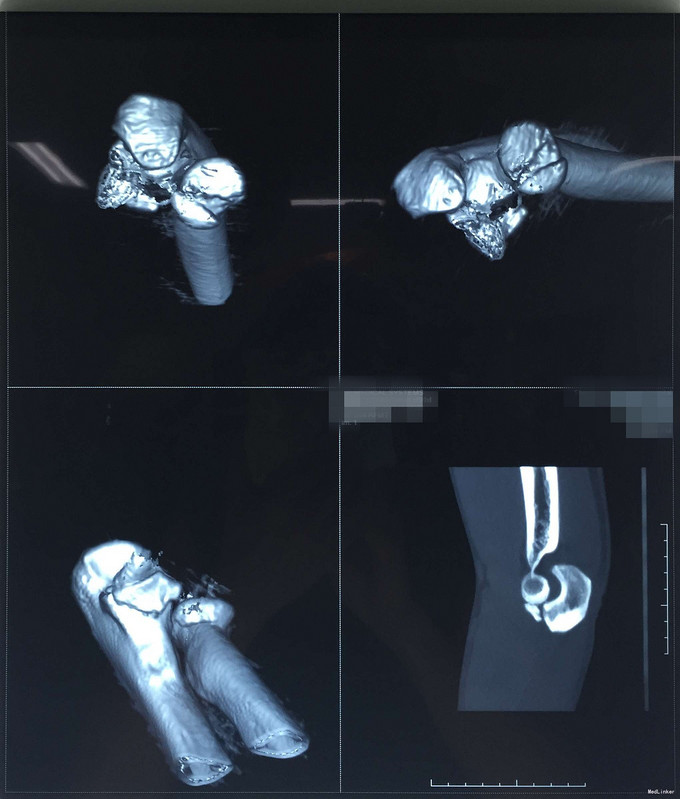

中年男性患者,因“高处坠落致左上肢及颜面部疼痛3天”入院。 患者3天前不慎从3米高处坠落致左肘部及颜面部受伤,即觉患处疼痛、活动困难,由同事送往西丽医院就诊,经行X射线提示左尺骨鹰嘴冠突骨折,左桡骨小头骨折,予缝合破裂嘴唇、固定牙齿及左上肢石膏固定等对症处理。今为做进一步诊治,患者来我院要求手术治疗,门诊拟“左肘关节骨折”收入我科。患者受伤以来,精神好,无呼吸困难,无恶心、呕吐,无头晕,无大小便失禁史。

体温36.7℃ 脉搏:100次/分 R:20次/分 血压:125/85mmHg。 神清合作,应答切题、全身皮肤黏膜无黄染、浅表淋巴结无肿大,头颅五官无畸形,巩膜无黄染,双侧瞳孔等大等圆,直径3mm,对光反射灵敏。颈软,无抵抗,气管居中,甲状腺无肿大,胸廓无畸形,胸廓挤压痛(-),心前区无隆起,双肺叩诊清音,呼吸清音,无干湿性罗音,心率100次/分,律齐有力,各瓣膜区无病理性杂音。腹平,腹肌软,全腹压痛、无反跳痛,肝脾肋下未及,双肾区无叩痛,无移动性浊音,肠鸣音存在,4-6次/分。左上肢检查详见专科情况,其余肢体检查正常,双侧生理反射存在,病理性反射未引出。 专科情况:左上肢轻度肿胀,无畸形,局部皮肤稍亮,局部轻压痛,纵向叩击痛,未扪及骨擦感,无反常活动,患肢手指肌力Ⅴ级,无手指牵拉痛,左上肢手指末梢及血运良好。 CT:左尺骨鹰嘴冠突骨折,左桡骨小头骨折

完善检查,行左尺骨鹰嘴冠突骨折+左桡骨小头骨折切开复位内固定术